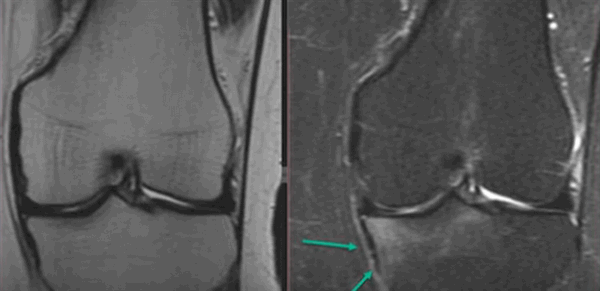

Нормальный левый коленный сустав на МРТ (красным выделен латеральный мениск, голубым — медиальный)

МРТ коленного сустава.В норме на МР-томограмме коленного сустава хрящ (яркий) покрывающий суставную поверхность имеет равномерную толщину, суставная поверхность имеет ровную форму, возможно минимальное количество жидкости, мениск имеет гипоинтенсивный МР-сигнал. У молодых людей имеется гипернтенсивный сигнал в метаэпифизе — зона роста (яркий МР-сигнал).

Суставная щель не сужена, конгруэнтность суставных поверхностей сохранена. Суставные поверхности четкие, ровные. Сигнал хрящевого компонента сустава не снижен; суставной гиалиновый хрящ относительно равномерный, толщиной 0,2-0,4 см.